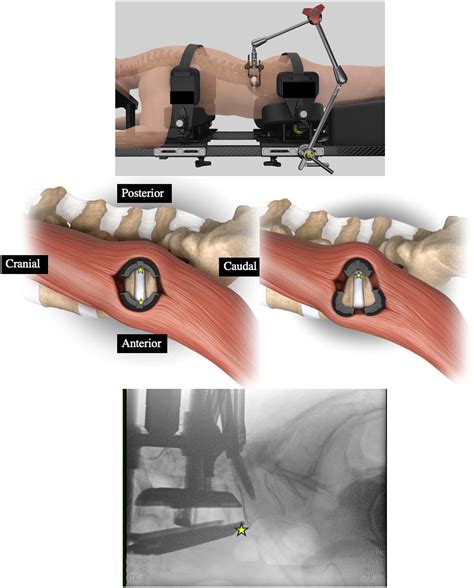

Patient Positioning

The patient is positioned supine (lying on their back) on the operating table. This position allows the surgeon to access the spine from the front of the body. The abdomen is prepped and draped in a sterile manner to minimize the risk of infection.

Incision and Approach

The surgeon makes a small incision in the lower abdomen, typically just above the pubic bone. The abdominal muscles are carefully retracted to expose the spine. The surgeon then identifies the affected vertebrae and disc space.

Disc Removal

The damaged disc is removed using specialized instruments. This step is crucial as it creates space for the bone graft or implant. The surgeon takes care to preserve the surrounding nerves and blood vessels.

Bone Graft or Implant Insertion

A bone graft or implant is inserted into the disc space. The graft can be autologous (from the patient's own body), allograft (from a donor), or synthetic. The implant is designed to promote fusion and provide structural support.

Minimally invasive surgical techniques have reduced the size of the incision and the amount of muscle trauma, leading to faster recovery times and less postoperative pain. These techniques use specialized instruments and imaging guidance to access the spine with minimal disruption to surrounding tissues.